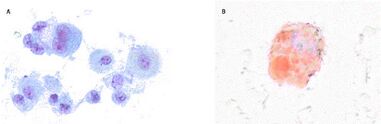

Первоначально врачи подозревали инфекционный характер заболевания. Макрофаги, обнаруженные у госпитализированных, могли вызывать воспалительный иммунный ответ, приводящий к липоидной пневмонии и другим пневмонитоподобным реакциям[3]. Так, у пациентов отмечались повреждения лёгких с патологическими проявлениями острого фибринозного пневмонита, диффузного альвеолярного поражения или организующей пневмонии, обычно сопровождающейся бронхиолитом, острой эозинофильной или атипичной пневмоний[13][10][4]. Некоторым пациентам был диагностирован химический пневмонит, другим — коронавирусная инфекция. Но поражения лёгких у госпитализированных с EVALI зачастую отличались от таковых у пациентов с коронавирусной пневмонией[4][13]. В ходе исследований не было обнаружено никаких доказательств инфекции, отсутствовала реакция на лечение антибиотиками[15].